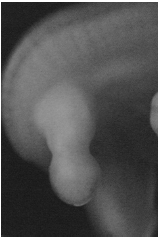

Desde hace varias décadas es muy dado que muchas comunidades prohíban a los niños que duerman en ciertas posiciones, que se sienten sobre sus pies o que los coloquen atrás y hacia los lados con las rodillas dobladas, posición comúnmente llamada en W (1),(2), en cambio, se obliga a que se sienten permanentemente con los pies hacia delante o cruzados en posición de indio o de Buda (Figura 1).

Figura 1. Posición frecuentemente corregida y la adoptada luego de que se lo ordenan. Nótese en este la misma posición intrauterina.

Después de revisar el desarrollo normal, podemos deducir que no son las posiciones en W (Figura 1), sentarse sobre los pies o dormir bocabajo las que producen valgo en las rodillas, anteversión femoral o torsión tibial, sino que éstas son posiciones que se adaptan a la evolución de la postura. Por otro lado, la posición de indio permanente (Figura 1), que también es contraria a la evolución normal de las rodillas y las torsiones femoral y tibial, podría considerarse como un vicio postural, incluso más grave que los primeros, puesto que de esta forma se mantienen las posiciones fetales de los miembros inferiores y la columna, que normalmente desaparecen con el crecimiento.